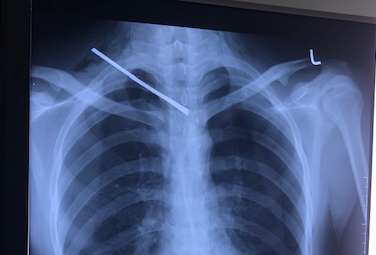

Ảnh chụp X-quang cho thấy thanh sắt đâm xuyên cổ bệnh nhân Dũng. Ảnh: Công an nhân dân |

Kết quả X-quang tim phổi thẳng cho thấy, một dị vật cản quang từ vùng cổ phải xuyên xuống đoạn gian đốt sống D3/D4, tràn khí màng phổi hai bên. Kết quả chụp CT64 lát cột sống cổ không cản quang phát hiện dị vật kim loại có đường kính 0.5cm, dài 10cm xuyên từ vùng cổ phải đến khe gian đốt sống D3/D4 chèn vào mặt trước ống tủy, tụ khí dưới da vùng cổ ngực hai bên, tràn khí và ít dịch màng phổi phải, tràn khí màng phổi trái.